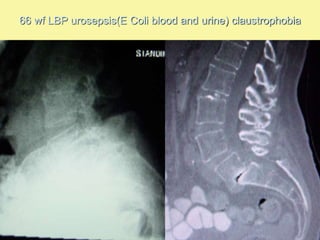

66 wf LBP urosepsis(E Coli blood and urine) claustrophobia